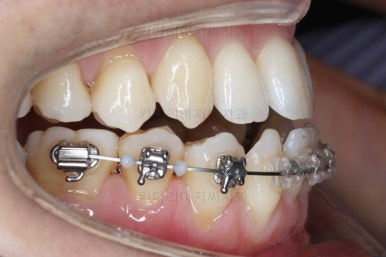

이 뽑은 자리로 앞니를 쭈욱 밀어넣으며 비대칭도 맞춰주기 위해서 미니스크류(마이크로 임플란트)라고 불리는 작은 나사를 잇몸뼈에 식립했어요.

이를 지지대로 삼아서 치아를 움직이게 됩니다.

아랫니를 계속 당겨주면서 가지런하게 하고 있어요.

어느 정도 진행이 되었다 싶으면 윗니도 장치를 부착해서 가지런하게 해줘요.

윗니도 장치를 부착했어요.

아랫니보다 해야 할 작업이 많지 않기 때문에 이렇게 시간차를 두어 진행을 했고, 이렇게 하면 교정장치가 눈에 띄는 기간이 줄어들어 환자분의 만족도는 더 올라가게 되죠.

아랫니 이 뽑은 자리는 거의 다 다물렸어요.

거꾸로 물리는 앞니도 어느 정도 많이 개선이 되었고요.